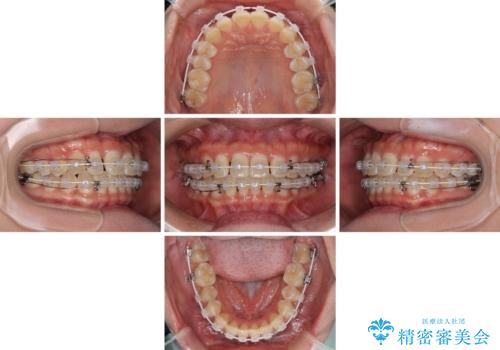

前歯の隙間と上下正中のズレを解消

- 矯正装置

- 審美装置

- 上下前歯隙間と正中のズレを改善したいとのことで来院された患者様です。

自己管理を減らしたいとのことで、ワイヤー装置による矯正治療を行うこととしました。

正中がなかなか合わずに、2年近くの治療期間を要しました。